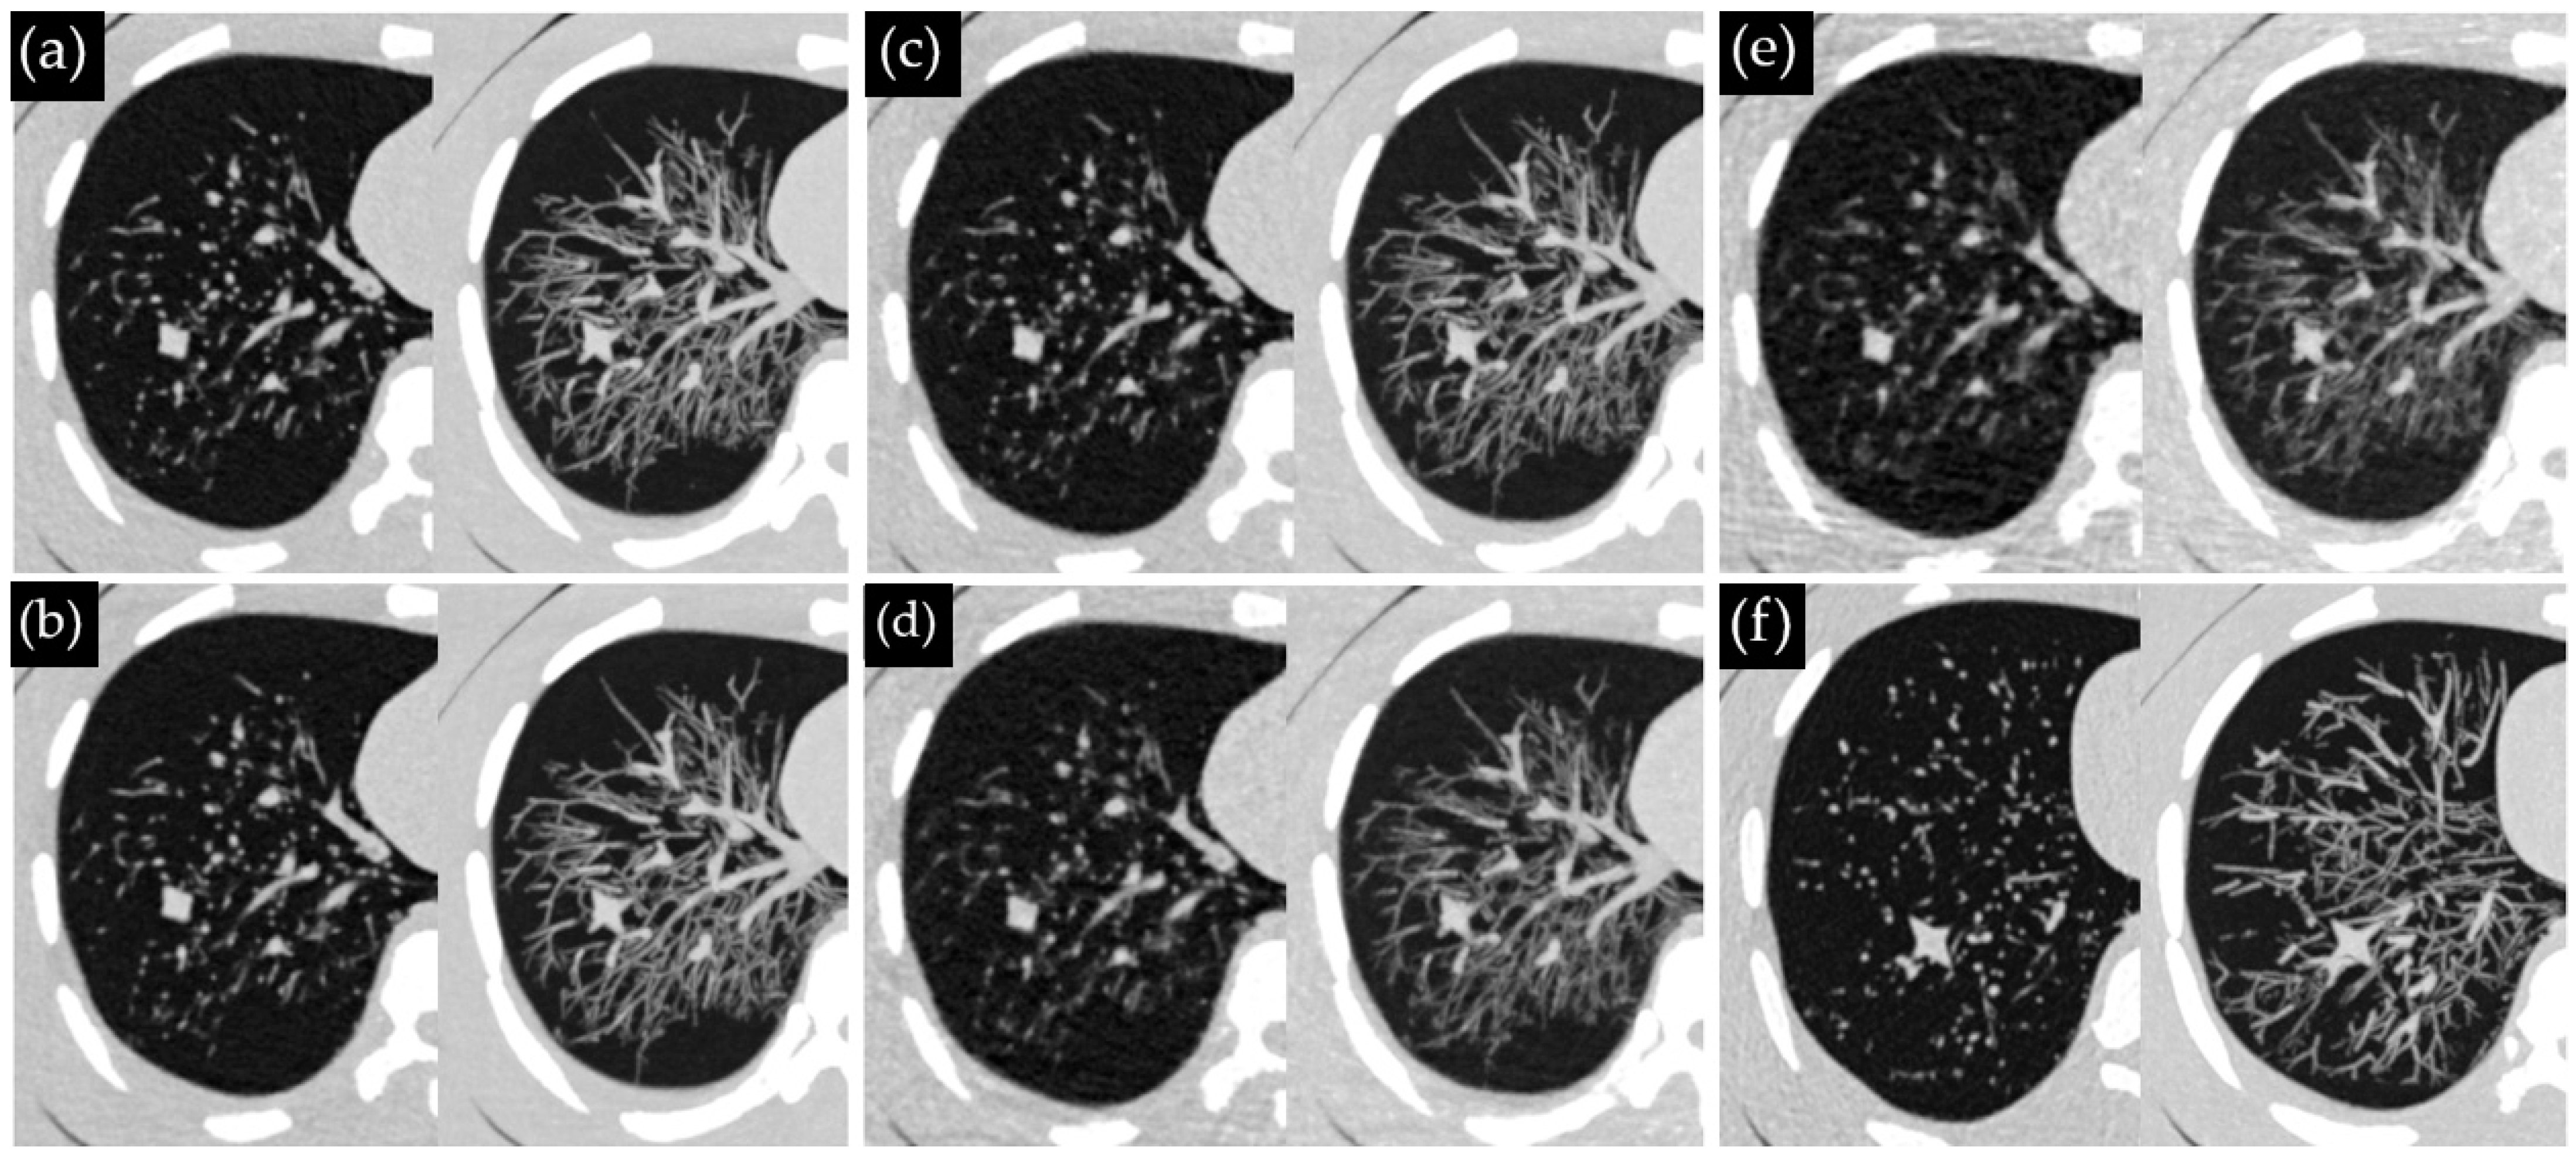

Figure 2 displays the representative thorax phantom images from EID-CT and PCD-CT. In 120 CT examinations, 642 nodules were present. This count included 36 nodules that were scanned three times across six CT protocols (five PCD-CT dose levels and one EID-CT protocol), as well as one nodule that was unintentionally scanned twice instead of three times. Observer 1 detected 367 nodules (57%), while observer 2 found 289 nodules (45%), with 383 nodules (60%) detected overall. The false-positive rates were 6.9% for observer 1 and 1.4% for observer 2. The inter-observer agreement was substantial (κ = 0.65).

Figure 2. Visual representation of CT image slices of the thorax phantom acquired using PCD-CT at (a) 100%, (b) 75%, (c) 50%, (d) 25%, (e) 10% of the reference dose and (f) EID-CT. The left and right images in each sub-figure represent 1.0 mm axial slices and 10 mm maximum intensity projection slices, respectively.